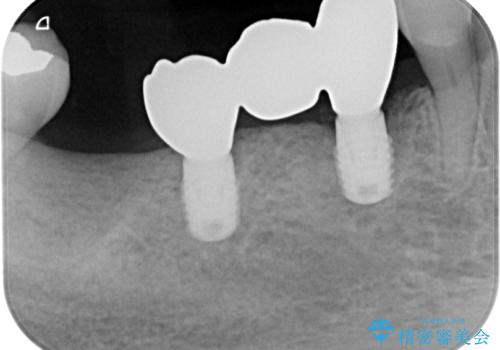

インプラント埋入時に仮歯を装着させることが可能な安定値が得られたため、その日に仮歯の装着を行いました。

咬合時に仮歯が噛み合わないように調整はしたのですが、反対側の奥歯も欠損していることから、食事中積極的に仮歯で咀嚼をしてしまい、2週間後には大きく安定値が低下してしまいました。

仮歯を速やかに撤去して力が一切かからない状態とし、1か月後と2か月後にそれぞれ安定値を測定することしました。

2か月後には無事に値が回復したため、セラミッククラウンにて補綴治療を行いました。